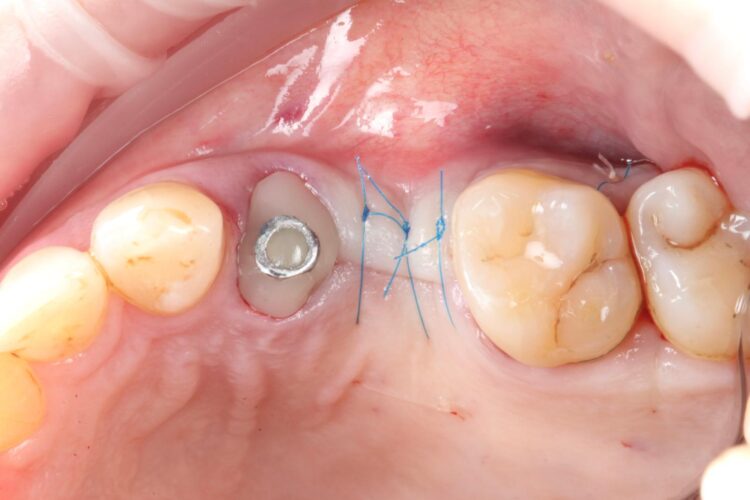

The implant in the UL5 was uncovered 3 months later to reveal healthy tissues. Three weeks later the final scan was taken (using trios intra-oral scanner) for the fabrication of the definitive crowns. On the day of crown fits both abutments were removed and the crowns seated. Due to the UL4 site having a custom healing abutment, which had been supporting our ideal emergence profile, it was much easier to engage this restoration and seat within the already moulded soft tissues.

With regards to the UL5 there was some blanching around the buccal aspect of the crown due to the use of a generic abutment, which does not offer any resemblance to the ideal emergence profile for the final restoration. Regardless good prosthetic positioning had been achieved to allow for screw-retained restorations in both implants. The final restorations were fitted as single unit layered zirconia crowns on titanium bases. The patient was delighted with the results.

Upon reflection of this case, a custom healing abutment may have delivered better soft tissue contouring than the generic abutment on the UL5. Healing may have taken longer, but it would have been easily tolerated by the patient and may have resulted in a better biological result with optimised aesthetics.